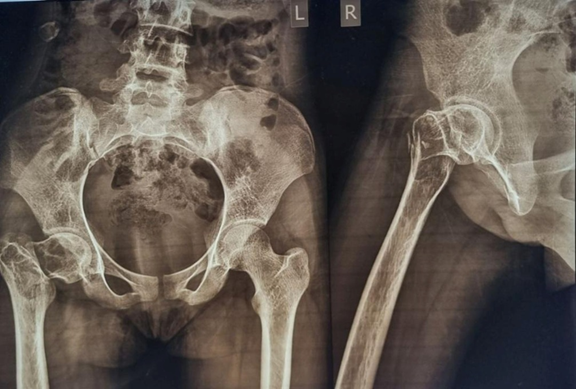

Blood investigations revealed elevated lactate dehydrogenase levels and a positive tartrate-resistant acid phosphatase test, signifying the aggressiveness of the tumor. The patient also had reduced hemoglobin levels. Radiographic evaluation revealed diffuse swelling of the proximal femur characterized by a mix of osteoblastic and osteolytic zones extending to the epiphyseo-metaphyseal region. The femoral head exhibited significant destruction, accompanied by notable soft-tissue involvement. A “soap-bubble” appearance was apparent, with radio-dense material in situ, indicative of remnant bone cement. The chest radiograph was normal.

Magnetic resonance imaging (MRI) demonstrated a large, inhomogeneous, expansile, and infiltrative lesion measuring 12.3 × 14.9 × 12.1 cm, involving the right hip joint and surrounding periarticular tissues. The lesion infiltrated adjacent soft-tissue structures and caused significant erosion of the femoral head. Residual bone cement material was also evident, indicating recurrence (Fig. 3).

Figure 3: Magnetic resonance imaging showing a large tumor at the proximal femur, along with a skip lesion at the distal femur.

High-resolution computed tomography (HRCT) of the thorax revealed multiple parenchymal and pleural-based lesions in both lung fields, consistent with metastatic disease. Core needle biopsy confirmed the diagnosis of a GCT. The tumor was classified as Enneking Stage III malignant GCT.

The distal femur exhibited an osteolytic lesion with a characteristic “soap-bubble” appearance. The patient was asymptomatic with regard to this lesion. Radiologically, the lesion showed epiphyseo-metaphyseal extension and was well-contained without any cortical breach. MRI findings also suggested a likely GCT. A core needle biopsy confirmed the diagnosis. Neoadjuvant denosumab, a RANKL inhibitor, was administered subcutaneously at a dose of 120 mg on days 1, 8, 15, and 28, followed by maintenance doses at 4-week intervals for a total of six doses. This pre-operative treatment regimen resulted in the formation of adequate surgical margins. Notably, denosumab therapy enabled surgical resection of the previously unresectable tumor.